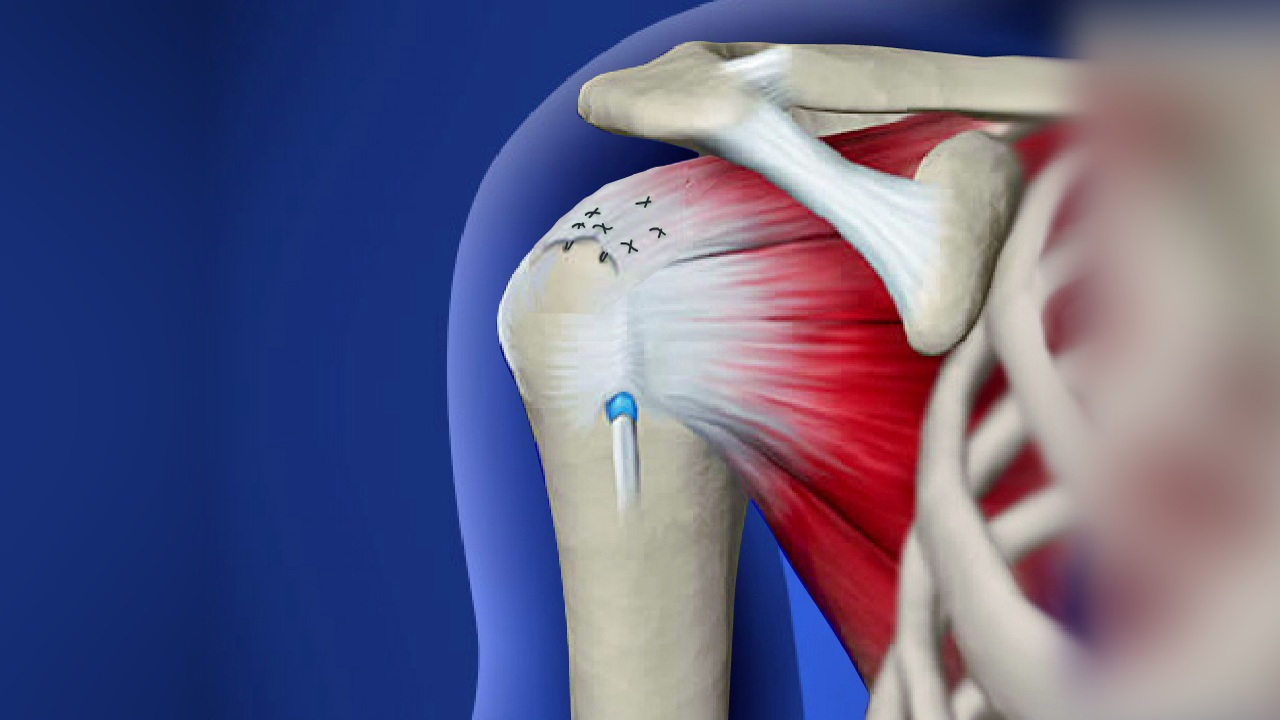

Фотографии мышц ротаторной манжеты плеча